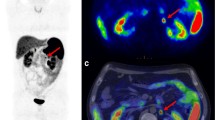

Graphic abstract